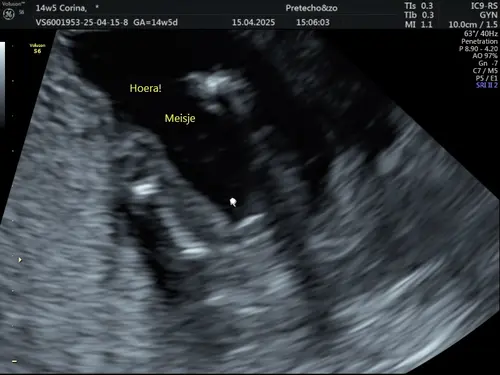

Nee dit was van mijn eerste, krijgen nu een meisje.

Nee snap dat jezelf ook twijfelt als zij ook twijfelt, maar het lijkt op de echo altijd groter dan het is, maar ben benieuwd! Laat je het weten als ze het zeker weten 😁

Dit is wel oprecht waarom onze verloskundige geen geslachtsecho’s maakt voor 16 weken😬 laat je weten wat het uiteindelijk is als je geweest bent?😘

Ik laat het zeker weten zodra het zover is, ben erg benieuwd en wat een verschil in echo's er zijn he😶 bij de een is het zo duidelijk zichtbaar en bij de ander denk ik waar kijk ik eigenlijk naar..